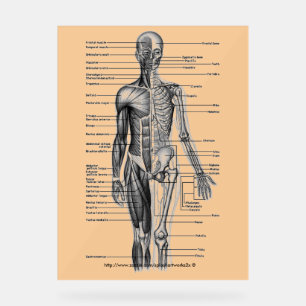

Anatomy of The Human Body Poster

PriceCA$66.35

Anatomy of The Human Body Canvas Print

PriceCA$185.00